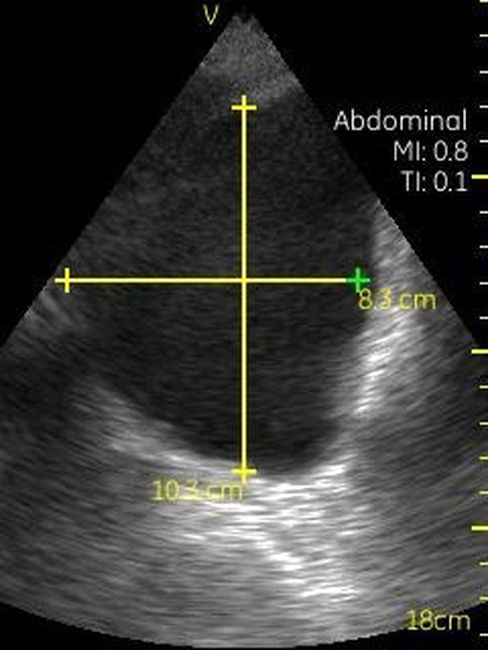

Визуализация Vscan:

· Черно-белый режим для визуализации анатомических структур в реальном времени.

· Поле зрения в черно-белом режиме: до 75 градусов с максимальной глубиной 25 см.

Размеры и вес:

· Дисплей: 135×73×28 мм.

· Дисплей: 3,5 дюйма, разрешение — 240×320 пикселей.